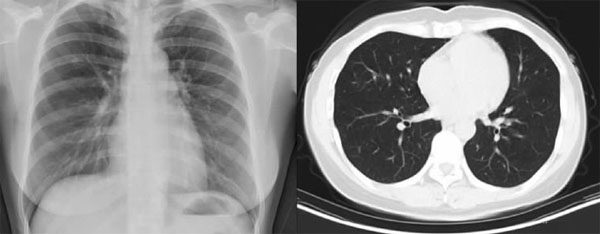

认识间质性肺炎

随着国内教育水平的提高以及互联网的普及,许多呼吸系统疾病,例如普通感冒、急/慢性支气管炎、肺气肿、肺炎、肺癌等,均已众所周知、耳熟能详。然而,公众对于近年来发病率逐渐增加的间质性肺炎(约占呼吸系统疾病就诊患者总数的15%)仍不甚了解,从而影响疾病治疗的依从性以及预防与管理。 什么是间质性肺炎 人体肺组织由实质和间质两部分组成。肺实质即肺内支气管的各级分支及其终末的肺泡结构,与空气直接接触。肺间

间质性肺炎的检查和治疗

气喘很痛苦,犹如溺水 正常的肺形象地讲,正常肺组织像是一个大海绵,肺泡就像海绵里众多细小的泡泡,每个泡泡都大致均匀大小,泡泡之间由于有周围结缔组织的固定而不能随意摆动,保证了呼吸的同步和效率。正常时,泡泡周围的结缔组织中有一些如钢筋混凝土中钢筋的纤维丝,即胶原纤维。这些“纤维丝”纤细轻薄,不会妨碍吸进来的空气中氧气弥散进入泡泡周围的血管里;同时保持了肺的弹性,肺脏不但可以自由的收缩呼出气体,还可